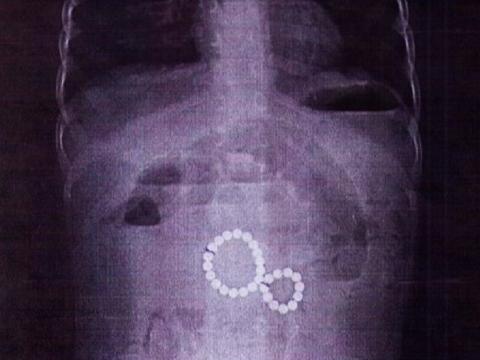

Ребёнка доставили в больницу в тяжёлом состоянии с симптомами кишечной непроходимости и рвотой с кровью. Рентген показал, что магниты попали в разные части кишечника и притянулись друг к другу, вызвав непроходимость и внутреннюю грыжу. Также существовала опасность разрыва стенки кишки.